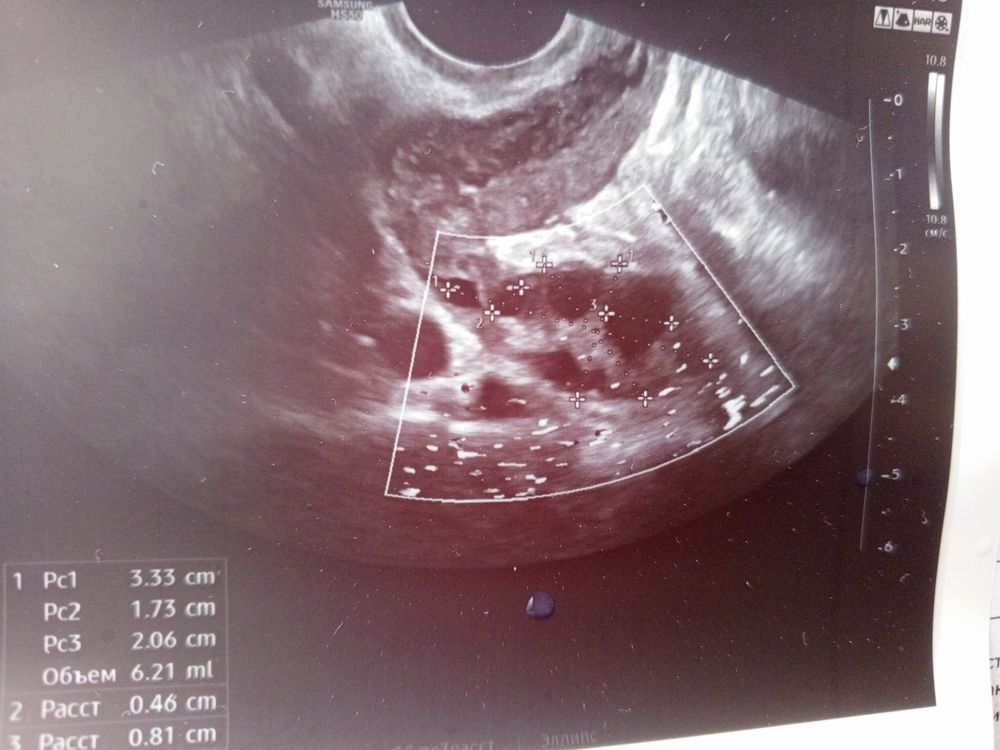

Фолликуламитрию на 13 дц

Первое узи Киста в сосудистом сплетении